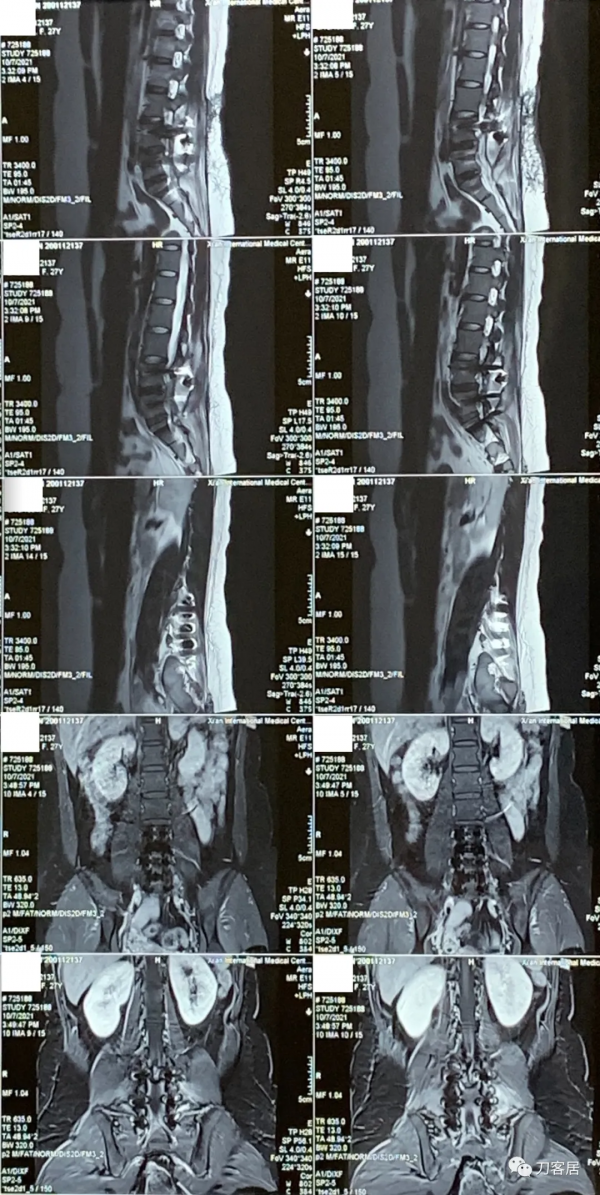

圖2. 20210817術前腰椎MRI矢狀面T2相,提示腰4-5,腰5骶1椎間盤突出,腰4-5椎間盤應該脫落進入椎管內,腰5椎體後緣了。

圖3. 20210817術前腰椎MRI矢狀面T2相,提示腰3-4-5-骶1椎間盤突出,腰3-4很輕,無需處理,腰4-5突出較大。

圖4. 20210817術前腰椎MRI矢狀面T1相,提示腰3-骶1椎間盤突出,腰4-5較大。

圖5. 20210817術前腰椎MRI橫截面掃描提示L3-4椎間盤輕度突出,左側旁中央型。

圖6. 20210817術前腰椎MRI橫截面提示L4-5椎間盤突出,較大,右旁側型。

圖7. 20210817術前腰椎MRI橫截面掃描,提示L5-S1椎間盤突出,右旁中央型。